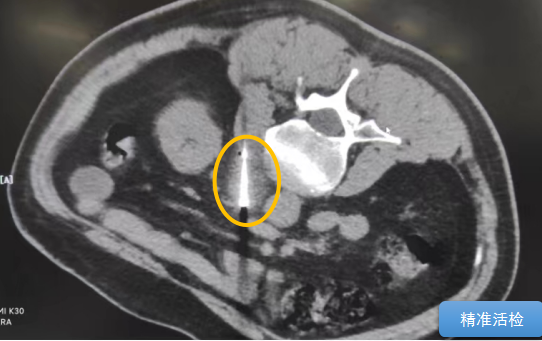

經(jīng)過(guò)多學(xué)科討論,陳寶瑩主任根據(jù)影像資料指出,患者轉(zhuǎn)移瘤位于腹膜后,內(nèi)側(cè)瀕臨人體最大的血管——主動(dòng)脈;前方同樣有血管緊貼腫瘤;外側(cè)是腎臟,后方是椎體和神經(jīng),夾縫中進(jìn)針難度大,治療時(shí)要避免周?chē)匾K器、血管和神經(jīng)的損傷,因此可以選擇CT引導(dǎo)下精準(zhǔn)穿刺活檢同步冷凍消融治療,即獲得病理組織有利于下一步全身治療方案的調(diào)整,同時(shí)殺死腹膜后轉(zhuǎn)移瘤,周?chē)=M織損傷的可能性也小。

術(shù)中陳寶瑩主任、李鐵柱教授、兀云飛醫(yī)生、魏東紅技師、汝平護(hù)士協(xié)調(diào)配合,夾縫進(jìn)針難度雖大,但在CT引導(dǎo)下逐步進(jìn)針,精準(zhǔn)到位,順利活檢取得組織,由于腫瘤較大,為了提高消融效率,平行置入兩根冷凍消融針,同時(shí)啟動(dòng)冷凍消融,術(shù)中清晰觀察到冰球完全覆蓋病變,患者沒(méi)有任何不舒服,治療中還可以和醫(yī)生聊天。